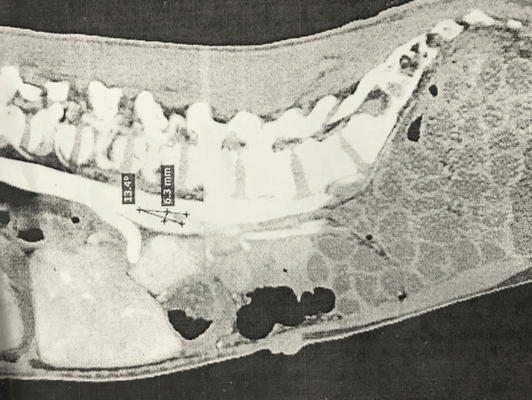

Пациент К., 25 лет обратился в клинику факультетской хирургии им. И.И. Грекова СЗГМУ им. И.И.Мечникова 29.11.2016 г. с жалобами на боли в эпигастральной области и левом подреберье, чувство тошноты, рвоту после каждого приема пищи, независимо от ее объема и характера, общую слабость и потерю веса на 15 кг в течении года. Из анамнеза заболевания выяснилось, что с 2011 года пациент стал отмечать наличие тошноты, рвоты, чувство тяжести в эпигастрии после приема пищи, в последующий год наблюдалось прогрессивное снижение массы тела (в 2012 г. m~65 кг.). Неоднократно обследовался, проходил лечение в различных клиниках . Так, по данным рентгенографии желудочно-кишечного тракта с контролем пассажа бариевой взвеси от 2014 г. отмечалось снижение моторно-эвакуаторной функции желудка, ДПК, висцероптоз (увеличенный в размерах желудок, ДПК, петли тонкой кишки на уровне малого таза). Кроме того, отмечалось замедление в эвакуации контраста из желудка и ДПК в дистальном направлении в течение 2 часов. После дополнительного обследования (данные пациентом не предоставлены) был установлен диагноз «стеноз чревного ствола», в связи с чем 03.02.2015 г. была выполнена: «Лапаротомия. Фундопликация по Ниссену. Декомпрессия чревного ствола». После операции пациент почувствовал улучшение общего состояния: отметил увеличение массы тела на 3 кг; прекратились тошнота и рвота после приема пищи. Однако через 2 месяца после оперативного лечения симптомы полностью возобновились. Больной находился под наблюдением гастроэнтеролога, получал консервативную терапию без существенного эффекта. При очередном обследовании, согласно данным рентгенографии с контрастированием желудочно-кишечного тракта от 08.11.2016 г., сохраняется замедленная эвакуация из желудка, ДПК, выраженный гастроптоз и дуоденоптоз. При этом эвакуация из пищевода в желудок составляет порядка 30сек., из желудка в ДПК около 1-2 мин, а эвакуация из ДПК до Трейтца 30-40 сек. Признаки спланхноптоза. По данным спиральной компьютерной томографии (СКТ) органов брюшной полости с контрастированием от 18.07.2016 г., отмечается дилатация нисходящей и горизонтальной части ДПК. Угол отхождения ВБА от аорты составляет 13,4 градусов (Рис 1).

Рис.1. СКТ- картина органов брюшной полости с контрастированием (стрелками указан угол отхождения ВБА от аорты)